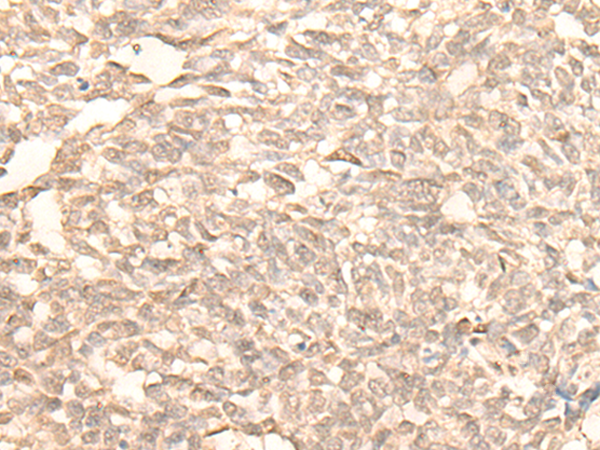

The image is immunohistochemistry of paraffin-embedded Human lung cancer tissue using 47184(RAD23B Antibody) at dilution 1/25. (Original magnification: ?00)